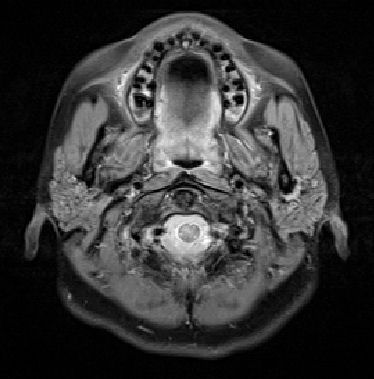

劇烈的頭痛八、九天了,不管吃任何一種止痛藥都只能暫時舒緩症狀,無法根除。白天痛,晚上也痛,尤其是右耳後方的後腦門,隨著脈搏的跳動,每天凌晨三點砰砰砰地將我痛醒。實在受不了去看醫生,他除了開處方用更強的止痛藥給我外,也讓我去做腦部磁振造影檢查 (MRI/MRA)。

做磁振造影比做電腦斷層掃描 (CT Scan) 容易多了。記得上次做電腦斷層掃描,不但要禁食,還要喝造影劑,過程中要配合技師做吸氣吐氣,也許還加上靜派注射。此次做磁振造影只是躺在那裡,頭部固定,耳中雖然有耳塞,但機器運轉的轟隆轟隆聲還是聽得到,整個過程大約三十分鐘,因為不能動,我還小睡了一下呢。

技術人員說檢查結果會直接寄給醫生,但是她可以先給我影像的 CD 。一共照了兩百多張片子,回家馬上開電腦欣賞一番,我不是醫生,當然看不出個所以然,但觀看自己腦袋內部的影像倒是蠻有趣地。現在只能靜候結果,希望一切平安無事。